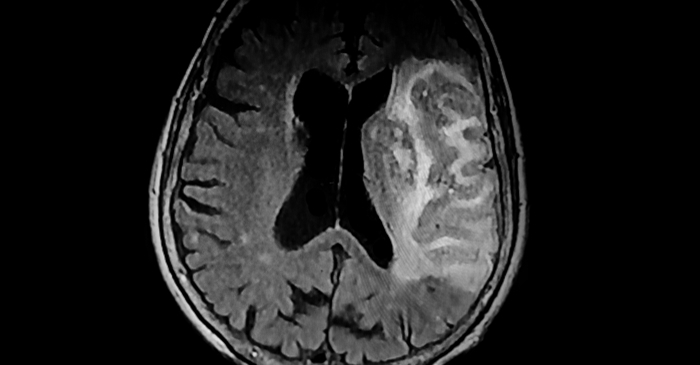

침묵의 살인자, 뇌졸중의 위험한 그림자

질병관리청은 10월 29일 ‘세계 뇌졸중의 날’을 맞아 “뇌졸중은 빠른 인식과 즉각적인 대처가 생명을 지키는 관건”이라며 조기증상 숙지의 중요성을 강조했다. 뇌졸중은 암, 심장질환, 폐렴에 이어 국내 사망원인 4위를 차지하는 중증 질환으로, 뇌에 혈액을 공급하는 혈관이 막히거나(뇌경색) 터지면서(뇌출혈) 뇌세포가 손상되는 병이다. 혈류 차단이 몇 분만 지속돼도 뇌 조직이 괴사하기 때문에, 초기 대응이 늦으면 생존하더라도 반신마비나 언어장애 같은 중대한 후유증을 남길 수 있다.